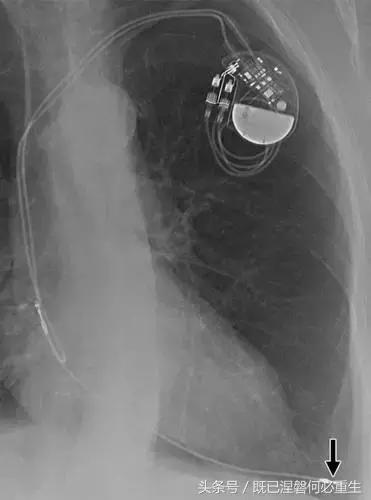

图。 6A 75岁的男性患有心房导线脱位。

A,Medtronic双腔起搏器的右心房导联(箭头)显示在正面(A)和外侧(B)图像上的纯垂直路线。 电极在心房中自由浮动。 患者抱怨经常心悸,并且设备检查显示不能可靠地去极化心房。 心房导线修订(未示出)导致心悸消除。 心房导线的推荐放置位于右心耳,但右心房中的导联可充分发挥作用。 在任一位置正确固定到壁上的引线通常将显示一定程度的曲率。